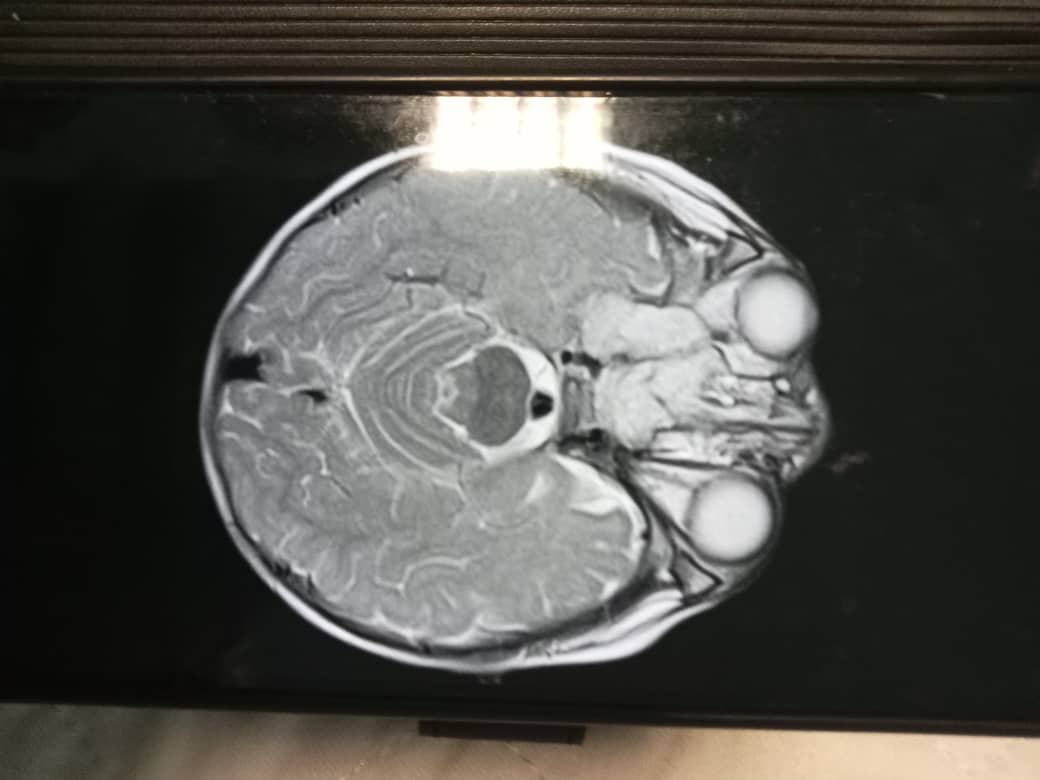

IPOH: A one-year and two-month-old baby, Firas Affan Mohd Fauzi, is undergoing intensive treatment after being diagnosed with cancerous tumour, specifically an extragonadal germ cell tumour (EGCT), on the right side of his face.

The condition was first noticed when Firas Affan experienced pain in his nose, followed by swelling near his right eye. His father, Mohd Fauzi Saad, 43, said the changes became apparent when his right eye began to protrude, and the right side of his face appeared pulled.

“He is improving and no longer cries daily. However, doctors have informed us that a tumour remains in his nasal cavity, and further surgery may be needed after all six chemotherapy cycles,” Mohd Fauzi added.

“Treatment costs are estimated at RM1,000 per month, including initial surgery and MRI scans. He now only drinks boxed milk, refusing powdered milk,” she said.